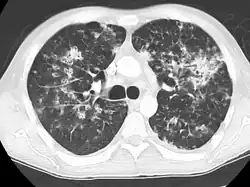

| Seu nome se refere a similaridade dos seus focos de infecção com grãos de milho espalhados pelo pulmão em 90% dos exames de raio-X. | |

A Tuberculose miliar ou tuberculose cutânea aguda disseminada é uma classificação médica internacional para um agravamento da tuberculose por sua ampla difusão dentro do corpo humano gerando pequenas lesões na pele (de 1 a 5mm).[1]